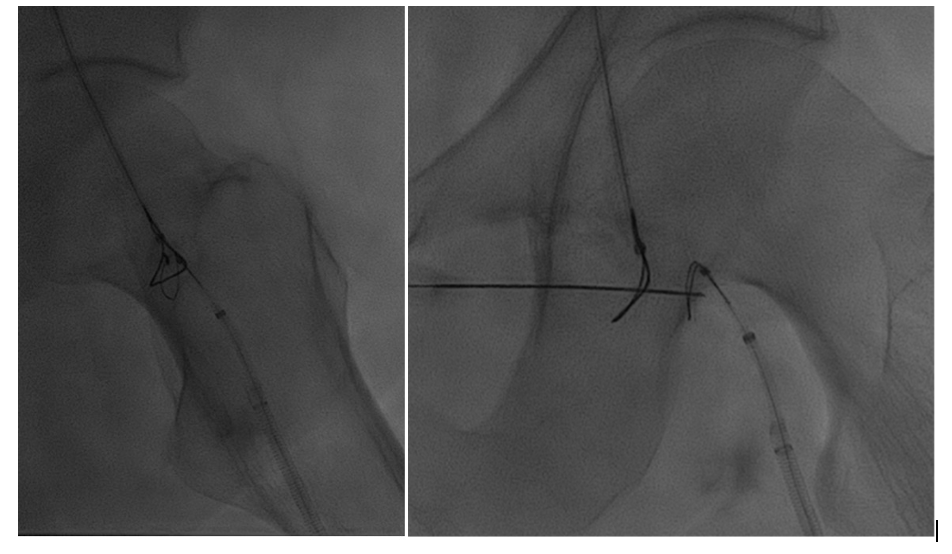

Using both ultrasound and fluoroscopy, we triangulated what we felt to be the appropriate trajectory for recanalization with safest access medial to the artery from a right anterior oblique approach (Figures 5 and 6).

Snare catheters (15-mm Amplatz Goose Neck [Medtronic]) were then placed bidirectionally and advanced to the most distal position in the truncated target channels. These were rotated to the appropriate position for planned recanalization. Percutaneous micropuncture access was then performed with ultrasound and fluoroscopy across both snare catheters, utilizing the modified gun-sight technique10 originally developed by Haskal et al11 (see Appendix).